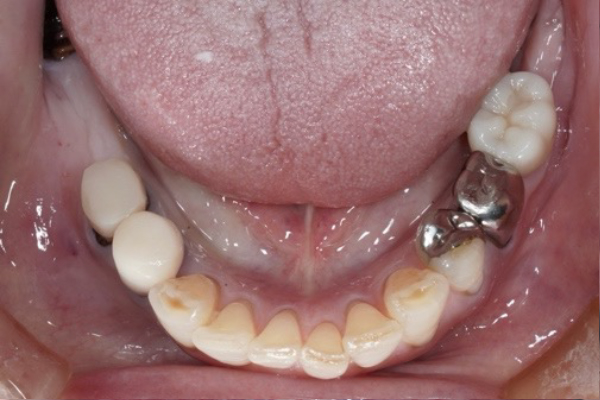

BEFORE

歯が揺れて咬めないことが主訴で来院されました。

重度に歯周病が進んでいる状態でしたので歯周病治療を行いインプラント治療を行いました。

かなり昔に奥歯の抜歯を行い、手前の歯から奥に伸ばして歯を作っている状態でした。このままでは、手前の歯にかかる負担が大きくなってしまい残すことが難しくなる可能性がありました。インプラント治療のメリット・デメリットを説明しインプラント治療を行うことになりました。

インプラント予定部位の骨が少なかったので、骨造成を行い、その後インプラント治療を行う計画を立てました。